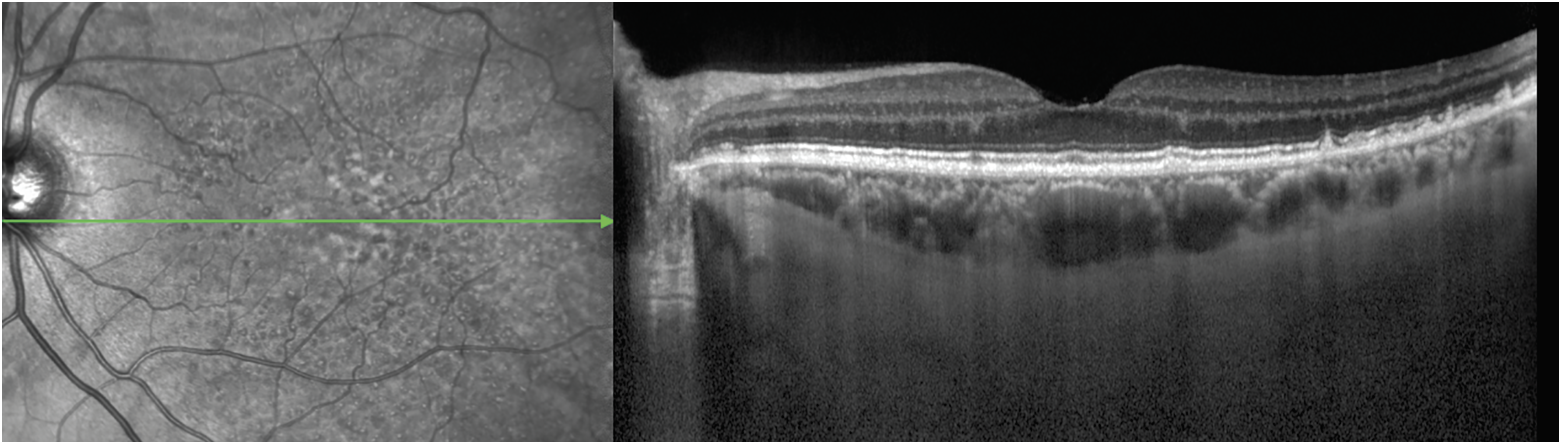

Grading RPD in clinical practice is achievable, since they’re detected most accurately on OCT (as well as near-infrared reflectance, which often accompanies OCT imaging – Figure 5).12,13 For clinicians less familiar with RPD grading, artificial intelligence algorithms will increasingly be available for automated detection, or the RPD-agnostic scale can be used.

![]() |

| Figure 5. Reticular pseudodrusen on near-infrared reflectance (left) and optical coherence tomography (right) imaging. The NIR image demonstrates the RPD as an extensive interlacing network of hyporeflective lesions surrounding by areas of hyperreflectivity. Some lesions have a target appearance. The OCT image shows the RPD as hyperreflective material above the retinal pigment epithelium, particularly in the far temporal macula. Some lesions are seen as mounds of hyperreflective material that alter the ellipsoid zone (EZ, i.e., stage 2), whereas others are conical and break through the EZ (i.e., stage 3; green arrow). Temporal to the fovea, soft drusen are also observed, comprising nonconical lesions of hyperreflective material below the RPE. |